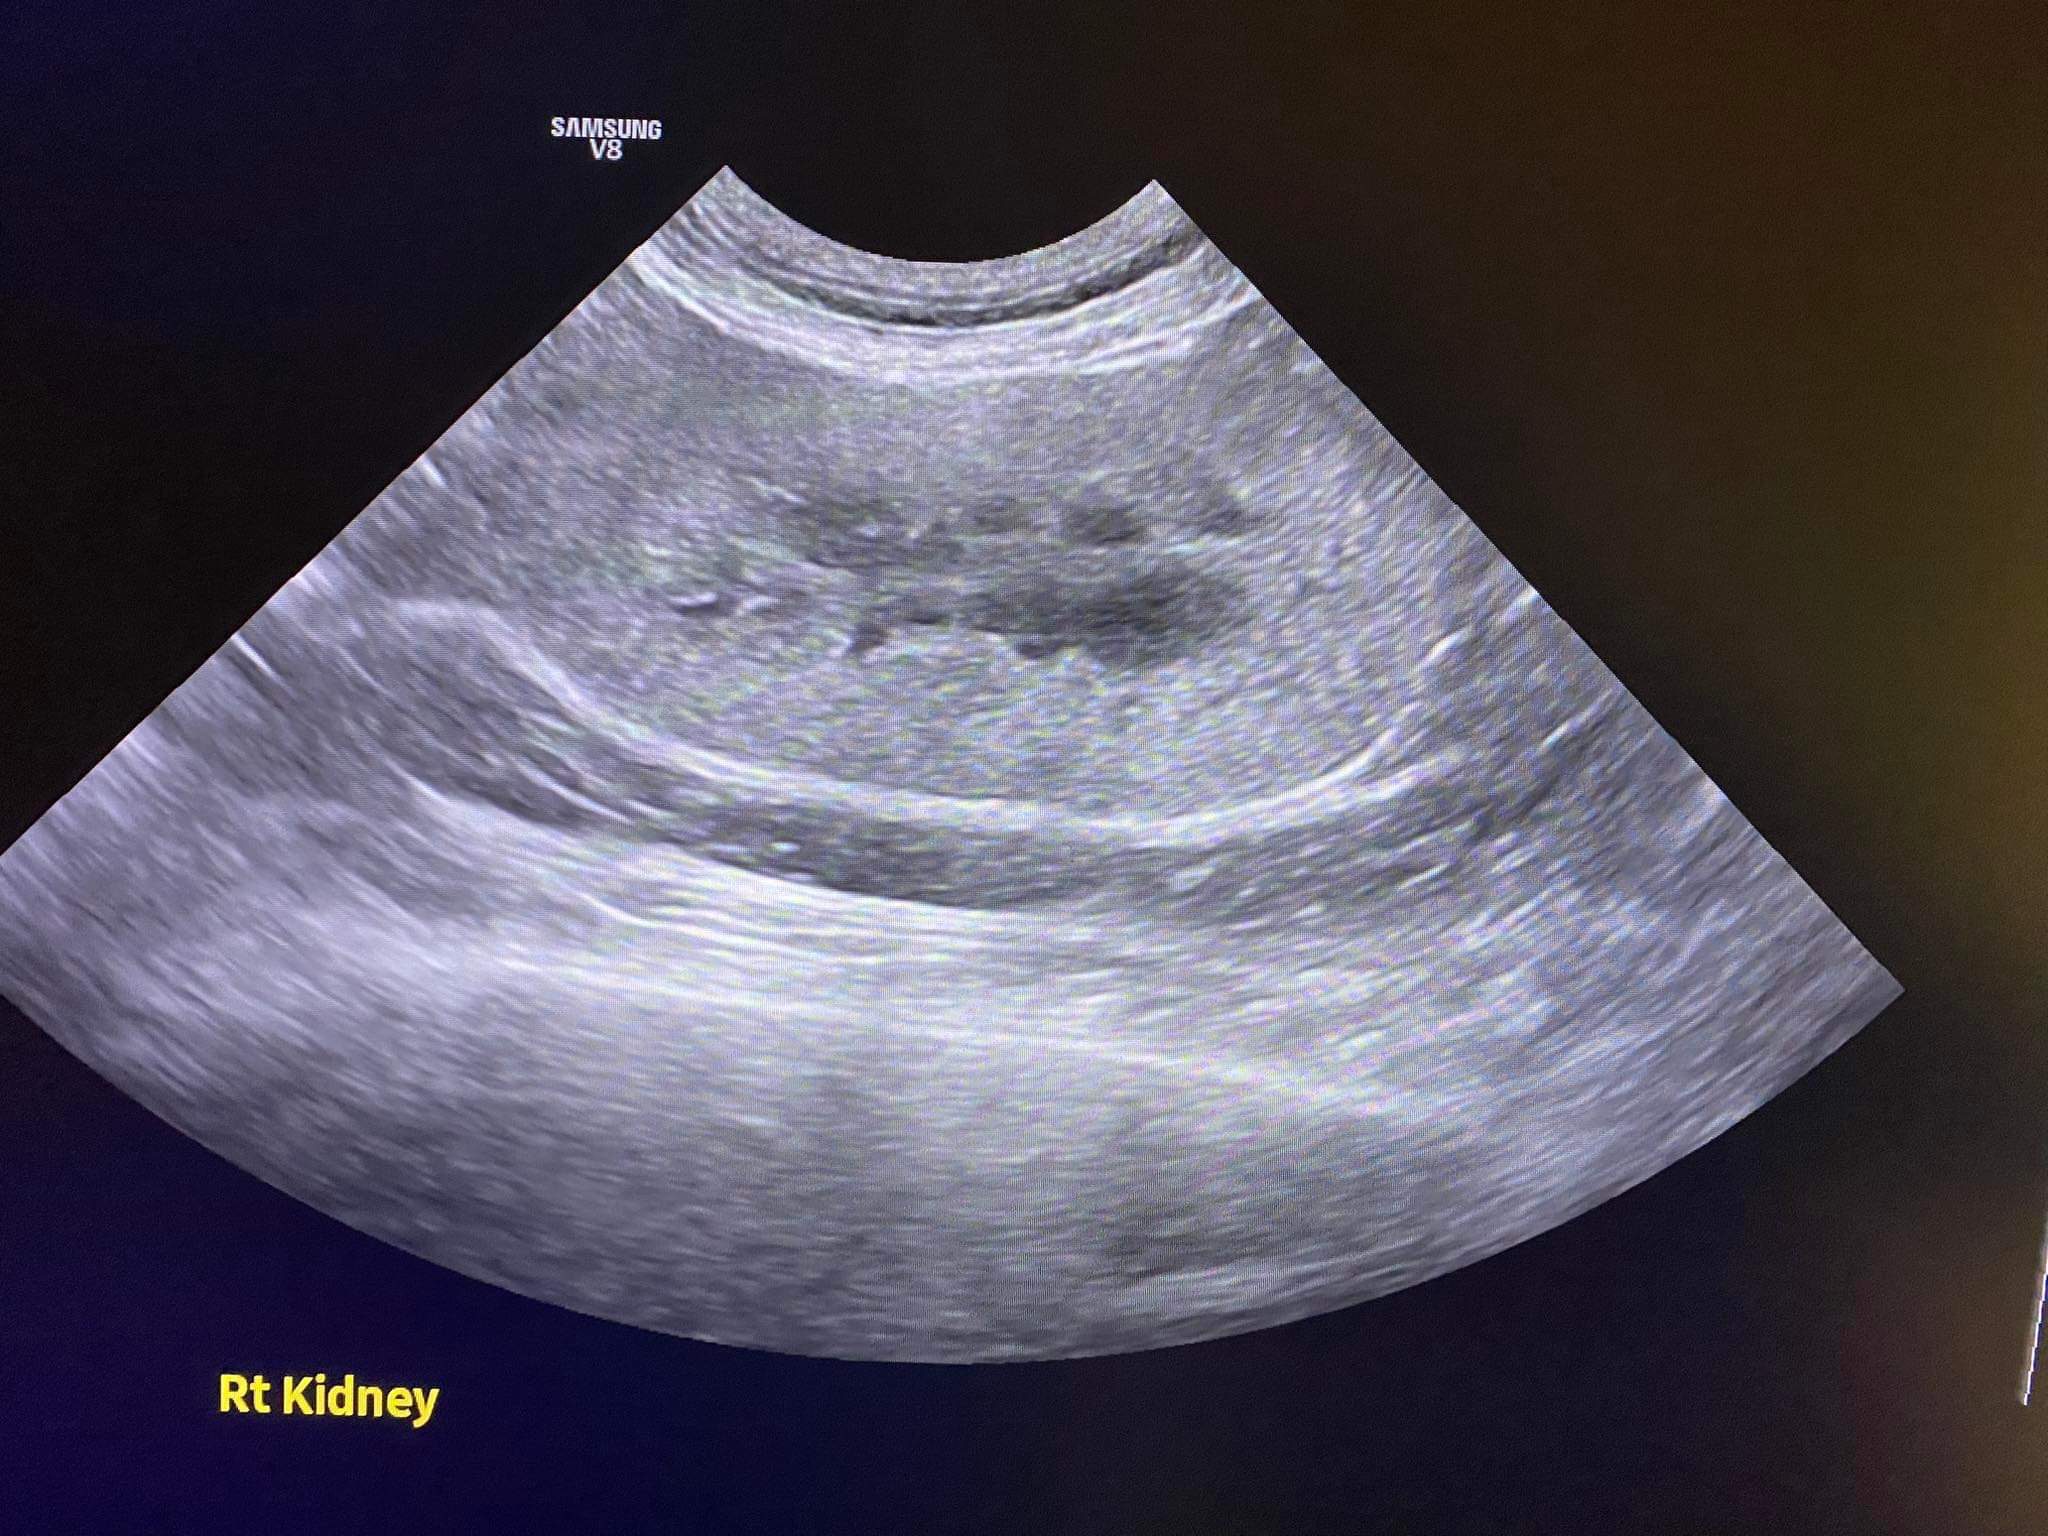

Going to do an abdomen u/s to check on his inner issue.

140pm u/s results r out:

Otherwise intestinal tracts fine, so his is not gastro issue. Is internal injury issue.

Conclusion: it’s highly likely that it’s dog attack. Trauma to the spleen and bladder and pancreas that cost pancreatitis now.